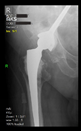

The guiding wire was inserted and controlled with fluoroscopy flashes (Figure 4). The drilling and reaming were carried out in accordance with the recommendations:

Figure 4.

The biocompatible aiming device after insertion of the guiding wire.

The direction of the cup stem was determined by the guide wire. The aiming device was needed to introduce this wire. After removing the aiming device, the next step was the drilling. Since a cannulated drill bit was used, the previously installed wire could guide the process. A self-positioning reaming tool was then used in the drilled channel. In the prepared cavity, the cup was fitted perfectly. Of the two stemmed cups available to us, the McMinn cup (Waldemar Link, Hamburg, Germany) had the simpler geometry and was therefore chosen. The stemmed cup was inserted according to the manufacturer’s recommendation. In the presence of a significant bone defect, a synthetic bone graft may be impacted for substitution.

The radiological examination allowed us to verify the close bone-to-implant contact and the unchanged position of the implant during follow-up.

In all the cases operated with the above-described targeting procedure, the stems of the cups remained between the cortical bone surfaces without perforation of the linea terminalis, as shown by postoperative radiographs. There were no complicated surgical situations. In 16 cases, the wound healings were uneventful, and the hips were able to bear weight again after postoperative rehabilitation.